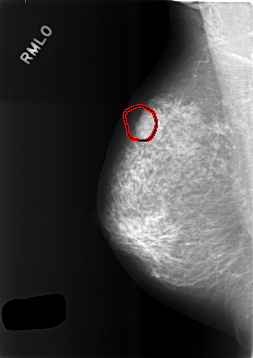

C_0475_1.RIGHT_MLO

RIGHT_MLO LINES 5720 PIXELS_PER_LINE 4040 BITS_PER_PIXEL 12 RESOLUTION 50 OVERLAY

FILE: C_0475_1.RIGHT_MLO.OVERLAY

TOTAL_ABNORMALITIES 1

ABNORMALITY 1

LESION_TYPE MASS SHAPE LOBULATED MARGINS MICROLOBULATED

ASSESSMENT 4

SUBTLETY 5

PATHOLOGY BENIGN

TOTAL_OUTLINES 1

BOUNDARY